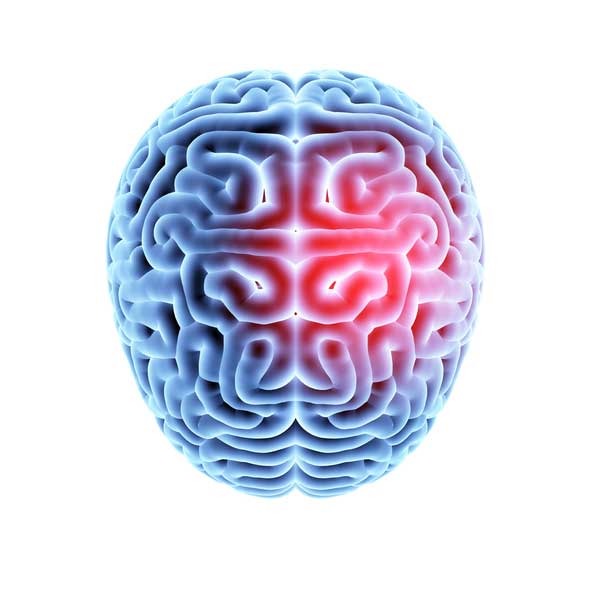

After a traumatic injury to the brain, grave damage may be done to the brain tissues and this can cause brain cell death. When these cells die, they can’t regenerate, and this can lead to a loss of brain function.

TBIs occur when the head is hit or shaken violently and can cause damage to the brain cells. This damage can lead to a variety of symptoms, including problems with thinking, sensation, language, and emotions. TBIs can be mild, moderate, or severe. Mild TBIs are also called concussions. Moderate and severe TBIs can cause long-term problems or even death.

However, for most traumatic brain injury treatments, adult stem cells are the most appropriate option. During a stem cell therapy procedure, stem cells are harvested from the patient’s own bone marrow and transplanted into the affected areas of the brain. However, after the procedure, the stem cells do not become neurons. Rather, they trigger the regenerative ability of the brain and the brain itself will create the new neurons.

The growth factors in the stem cells enhance the recovery chances of the brain and help to recover from traumatic brain injuries. In a way, these stem cells can turn your traumatized adult brain into an infant-like one with the ability to recover quickly from injuries.